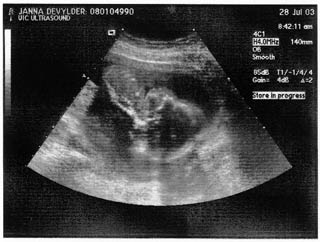

Here's a beautiful picture of our son...look at that spine! Look at that head! He's upside down in this... see his ribs?